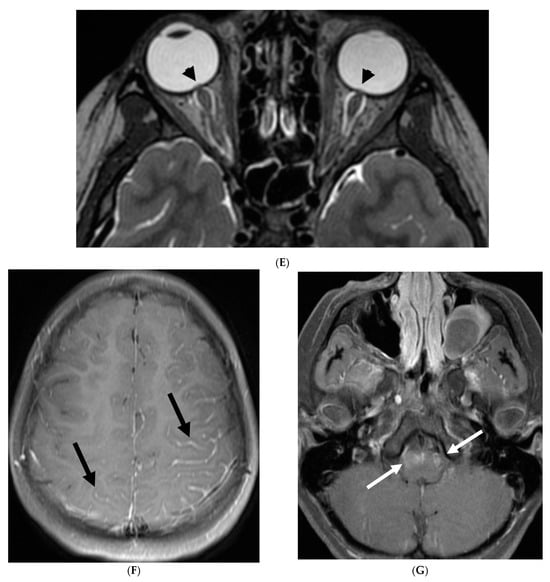

3.9. Alk-Positive Histiocytosis

ALK-positive histiocytosis (APH) is a rare, non-Langerhans cell histiocytosis that can involve the nervous system, including the meninges. While the disease is often seen in infants and young children, it can occur at any age [68]. Neurologic involvement usually presents as seizures, ataxia, headaches, and vomiting [69]. Imaging findings on CT include iso-dense or slightly hyperdense nodules/masses [70]. On MRI, lesions demonstrate isointense or slightly hypointense signals on T1-weighted, isointense or hypointense signals on T2-weighted, with moderate homogeneous focal or smooth ring enhancement [71]. Meningeal enhancement (Figure 10F) can appear segmental and be particularly prominent along the cauda equina [71]. Restricted diffusion is also commonly seen (Figure 10 and Figure 11) [69].

Figure 10.

Axial T2 (A), sagittal T1 post contrast (B), Sagittal T2 (C,E) and sagittal T1 post contrast (D,F): 20-month-old boy with 2 months of losing developmental milestones and 1 month of emesis, fatigue and dehydration. Ventriculomegaly with transependymal fluid is noted (black arrows). There is posterior fossa leptomeningeal nodular enhancement extending into the upper cervical spine (curved white arrows). Extensive nodular enhancement along spinal cord (dashed white arrows) with cord edema demonstrated in the entire cord (white arrows).

Figure 11.

3 weeks follow up: Post contrast sag T1 (A) and axial FLAIR (B), Axial T2 (C), sagittal T2 (D), Post contrast sagittal T1 (E) and PET/CT (F): Leptomeningeal nodular enhancement along posterior fossa, suprasellar and spinal cord (curved arrows) has significantly increased. There is also new/increased signal abnormality in the brain stem and cord (white arrows). Hypermetabolic spine disease is demonstrated on PET/CT. No osseous involvement is identified on the PET scan. Pathology: Diffuse CNS ALK (Anaplastic Lymphoma Kinase)-Positive Histiocytosis. Bone marrow biopsies, US abdomen and skeletal survey negative for extracranial/extraspinal disseminated disease.

Differentiating APH from other meningeal diseases can be challenging. The most important imaging differential is meningioma. Meningiomas are typically well-circumscribed, dural-based lesions that enhance intensely and homogeneously. Meningiomas often demonstrate a “dural tail”—a thin, linear enhancement extending from the main tumor mass along the dura mater [71]. Another important differential is juvenile xanthogranuloma (JXG), which can also involve the meninges. JXG lesions are typically well-defined, enhancing nodules that are often located near the ventricles or meninges [71]. Ultimately, a definitive diagnosis of APH requires histopathologic and molecular testing, which demonstrates the presence of ALK rearrangement, typically a KIF5B-ALK fusion [72].